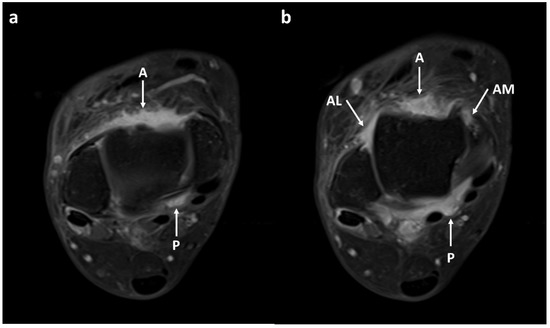

3.2. Synovial Visibility on FLAIR-FS and CE-T1 Images